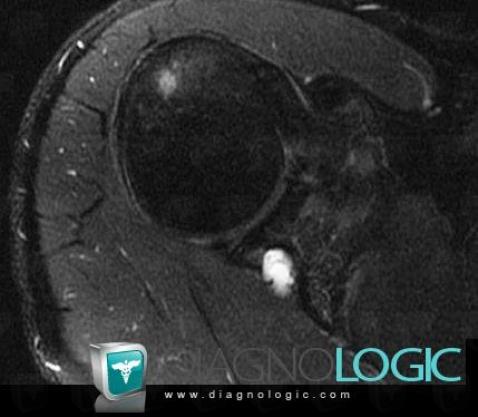

Perilabral cyst, Gleno humeral joint, Other soft tissues/nerves - Shoulder, MRI

- Diagnosis Perilabral cyst, Location(s) Gleno humeral joint, with gamuts Synovial mass or thickeningOther soft tissues/nerves - Shoulder, with gamuts Cystic and cystic-like soft tissue mass